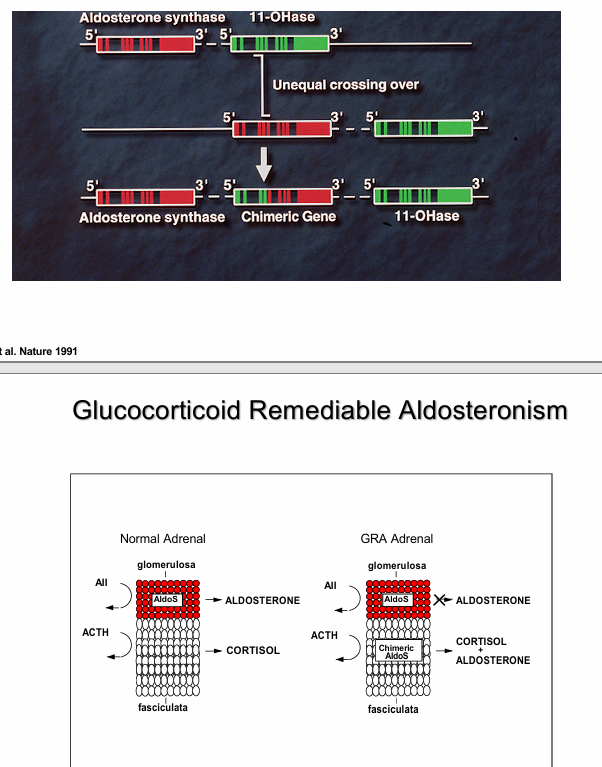

glucocorticoid remediable aldosteronism